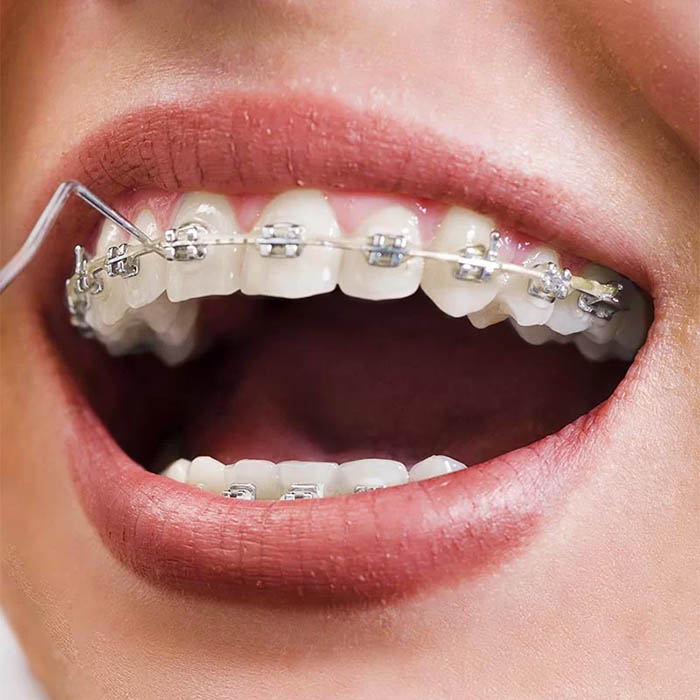

Rögzített fogszabályozó készülékek

Ezeket a készülékeket közvetlenül a fogazatra ragasztják. Két típusuk létezik: (1) a hagyományos, fémligatúrás rögzített fogszabályzók és az (2) önligírozó (önzáró) rögzített fogszabályzók.

Ez utóbbiaknál gyengédebben, kíméletesebben lehet mozgatni a fogakat. Az eljárást jól ki lehet egészíteni különböző típusú gumihúzásokkal, amikkel állkapocs pozícióbeli eltéréseket (pl. mélyharapást, nyitott harapást) lehet összehangolni.

A rögzített fogszabályozóknál használt ún. brackettek készülhetnek fémből és kerámiából. Ez utóbbi esztétikusabb, de drágább megoldás.